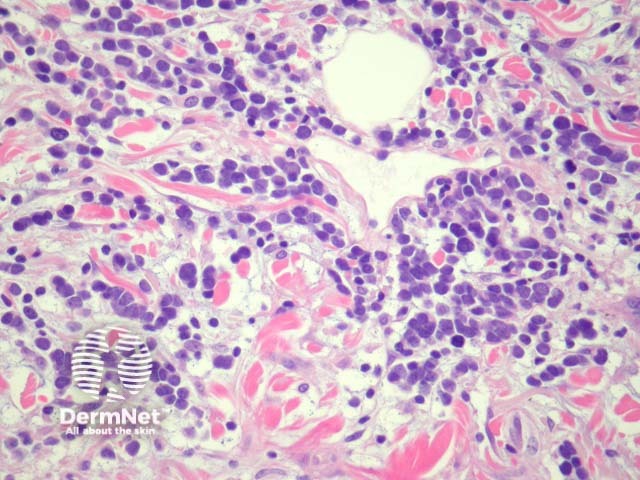

Merkel cell carcinoma is a neuroendocrine carcinoma composed of densely blue cells. The tumour is centered in the dermis with frequent involvement of the overlying epidermis (figures 1, 2) and may invade the subcutaneous fat. The tumour forms sheets, nests and rarely ribbons. The outlines of the cells often mold together or resemble lymphocytes (figures 3, 4). There are numerous mitoses, and there may be necrosis. Lymphovascular invasion is common.

Figure 3

Figure 4